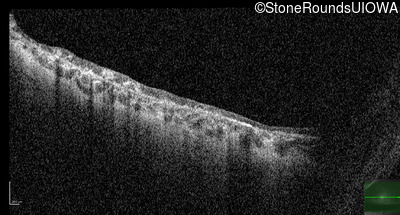

This 35 year old woman had vesicular skin lesions on her trunk and limbs first noted at 7 days of age. Peripheral retinal neovascularization was seen in both eyes at 4 months of age and cryotherapy was performed three times in the ensuing 6 months. An irreperable tractional detachment occured in the left eye during that period. She had her first seizure at age 6 years.